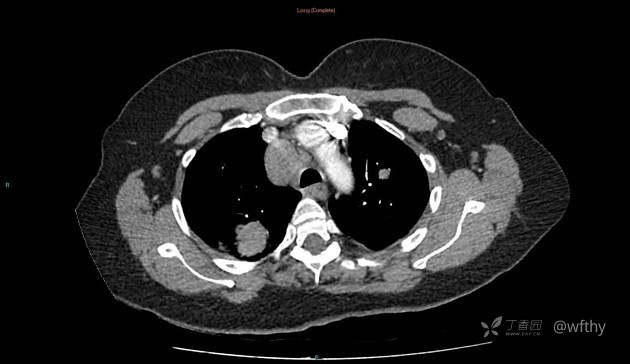

病例女65,头部肿块